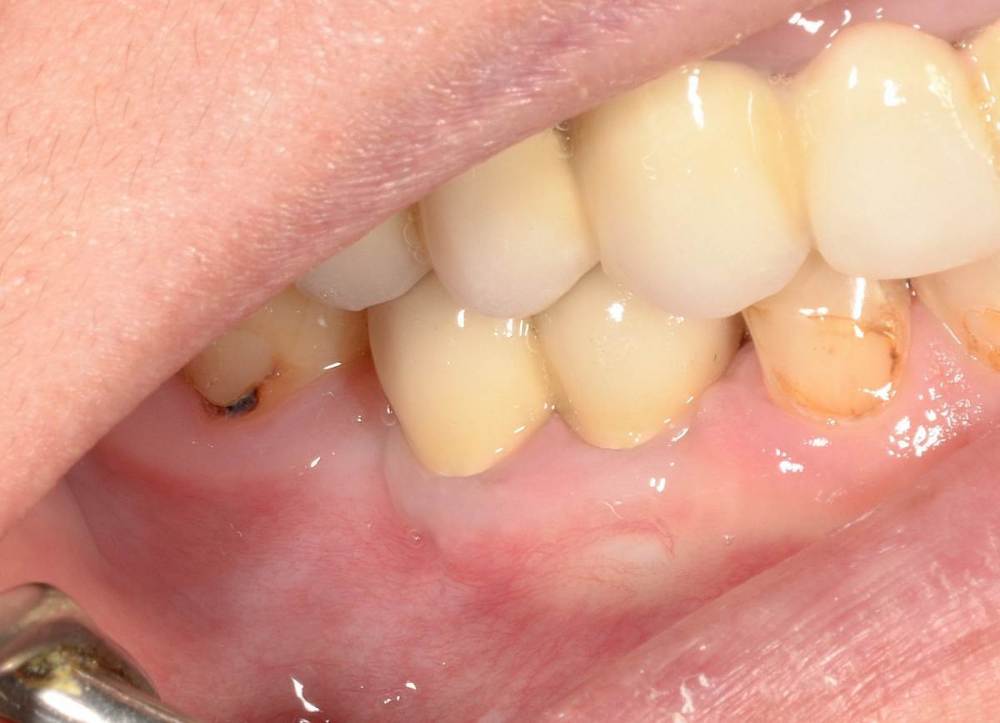

Большой Зеленый Опубликовано 27 мая, 2022 Поделиться Опубликовано 27 мая, 2022 Через 9 лет. Есть немного рецессии.. 2 Ссылка на комментарий

pit Опубликовано 27 мая, 2022 Поделиться Опубликовано 27 мая, 2022 4 часа назад, Большой Зеленый сказал: Через 9 лет. Есть немного рецессии.. Это связано исключительно с вестибулярной позицией импланта. Это как раз к вопросу про те минимальные 2мм до вестиболярной стенки, вне зависимости есть она или ты ее создаешь. Ссылка на комментарий

Большой Зеленый Опубликовано 27 мая, 2022 Поделиться Опубликовано 27 мая, 2022 4 часа назад, pit сказал: Это связано исключительно с вестибулярной позицией импланта. Это как раз к вопросу про те минимальные 2мм до вестиболярной стенки, вне зависимости есть она или ты ее создаешь. С тех пор я стал хитрее умнее и опытнее ))) 1 час назад, alboard сказал: А в чем смысл ее сохранности, если препарируя под имплантат вы все равно ее в большинстве случаев сносите? Первичная стабильность импланта зачастую достигается только перегородкой.. Ссылка на комментарий

Женька Опубликовано 27 мая, 2022 Поделиться Опубликовано 27 мая, 2022 @Большой Зеленый это вроде ваш старый кейс? напомните пожалуйста, тут присыпка+мембранинг вестибулярно и вестибулярным лоскутом слегка послабленным всё закрыли? Ссылка на комментарий

Большой Зеленый Опубликовано 28 мая, 2022 Поделиться Опубликовано 28 мая, 2022 12 часов назад, Женька сказал: @Большой Зеленый это вроде ваш старый кейс? напомните пожалуйста, тут присыпка+мембранинг вестибулярно и вестибулярным лоскутом слегка послабленным всё закрыли? Да все так и есть как Вы и описали. Работе почти 10 лет. Присыпка мп3 от остеобила сверху "ильгамовская" губка . Считаю что результат вполне удовлетворительный. Рецессия обусловлена как уже сказали выше вестибулярным положением импланта ,ну и недозаглублен чуток. Ссылка на комментарий